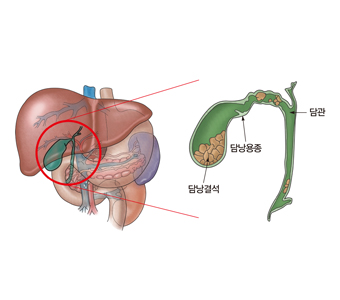

담낭 용종은 일반적으로 양성 용종을 지칭합니다. 양성 종양에는 콜레스테롤 용종, 염증성 용종, 선근종, 선종, 근종, 지방종 등이 있습니다. 악성 용종은 담낭암에 해당합니다.

담낭 용종은 대부분 병변 자체만으로는 증상이 없습니다. 간혹 우상복부 및 명치에 통증이 있을 수 있습니다. 담낭 용종이 담낭관을 막으면 담석으로 인한 통증과 비슷한 증상을 유발할 수 있습니다.

초음파 검사는 매우 정확해서 90% 정도의 담낭 용종을 발견할 수 있고, 용종을 담석 등 다른 질환과 구별할 수 있습니다. 담낭 용종을 좀 더 정밀하게 검사하기 위해서 내시경 초음파 검사를 시행할 수 있습니다. 이는 복부 초음파에 비해 진단의 정확도가 높습니다. 또한 악성 용종의 가능성이 높다면 복부 CT나 MRI가 도움이 됩니다.